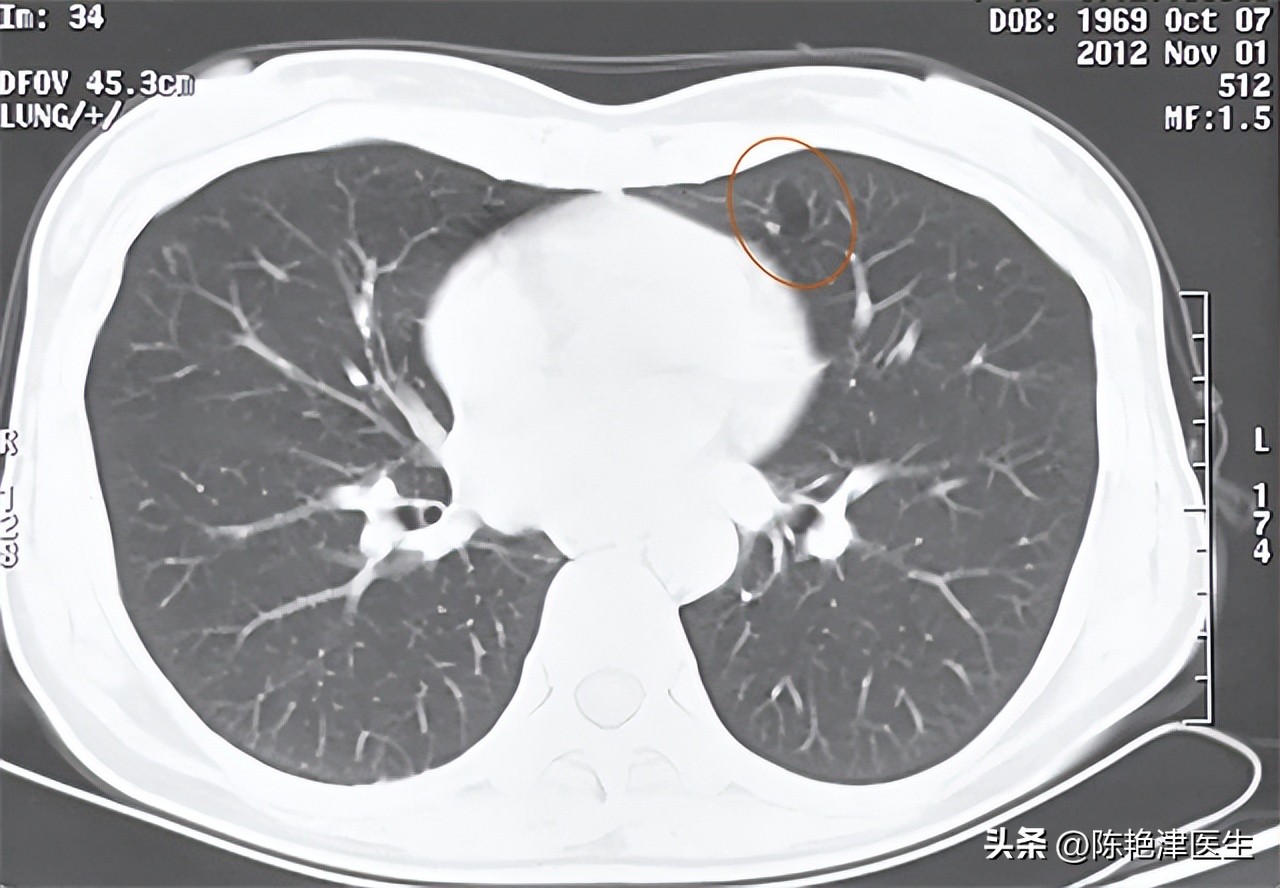

一般来说,对于大部分 无症状 、偶然发现的肺大疱,通常 不需要进行治疗 ,只需要定期 复查随诊 ,观察肺大疱有无进展即可。目前临床上常用的检查手段有以下三种。一种是 X线 检查,最廉价又最常用,但对于直径较小的肺大疱不易检出;

一种是 CT 检查,能够发现直径小于1cm的肺大疱【2】,较前者敏感;最后一种是 肺血管造影 ,用来明确周围血管的分布和被肺大疱挤压的情况,为手术治疗提供一定的参考。